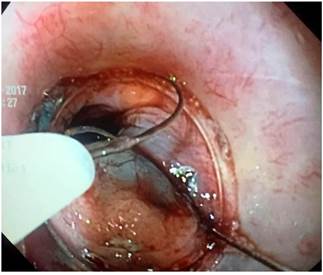

Se programó la resección de la lesión mediante una técnica de disección endoscópica de la submucosa (DES). Durante el procedimiento, posiblemente por el proceso de cicatrización secundaria a las biopsias realizadas, no se logró elevar satisfactoriamente la lesión mediante la inyección submucosa de solución salina con azul índigo carmín; por esta razón, se decidió cambiar la técnica de resección y se realizó la resección completa con el kit de mucosectomía endoscópica de Olympus, EMR Kit Modelo K-009 (inyector, cap angulada y asa de polipectomía) y con ayuda de la unidad electroquirúrgica ERBE VIO 200 S (modo endocut Q, efecto nivel 3, duración de corte 1 y con intervalo de corte de 6) (Figura 2). Finalmente, el parche de mucosa gástrica ectópica fue completamente resecada en 4 fragmentos, incluidos los focos de tejido adenomatoso. No se observó tejido columnar residual y no se realizó ablación de los bordes de resección debido a que no hubo sangrado y en consideración a que la mucosa columnar por sí misma no corresponde a una lesión premaligna (Figura 3).